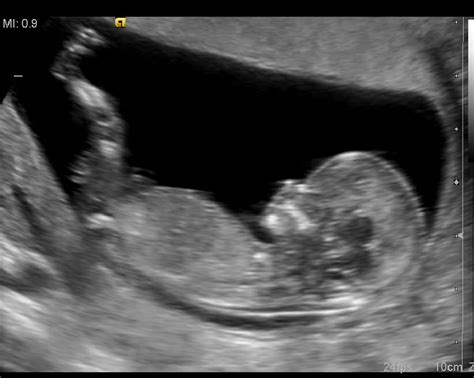

V 36. tednu nosečnosti vaš dojenček postaja vse bolj podoben novorojenčku. Tehta že približno dva kilograma, na teži pa pridobiva zelo hitro, vsak dan okrog 30 gramov. Njegova dolžina meri že okrog 50 centimetrov. Če bi se rodil sedaj, ne bi imel več nobenih večjih težav, saj so njegovi organi že dozoreli in je pripravljen na življenje izven maternice. Telo otroka je še vedno pokrito s sirastim in mastnim premazom, imenovanim verniks, ki ščiti njegovo kožo. Možgani so že dobro razviti, čeprav še vedno poteka intenziven razvoj živčnih povezav. Jetra, ledvice in pljuča so popolnoma pripravljeni za izvenmaterično življenje. Otrok že sesa palec, diha in požira plodovnico, kar pomeni, da so mišice in organi, ki sodelujejo pri hranjenju in prebavi, dodobra pripravljeni na prvo hranjenje z materinim mlekom. Njegovi možgani so sposobni usklajevati gibe, kar že kaže na kompleksnost njegovega razvoja.

Od 36. tedna naprej se večina plodov že obrne z glavico navzdol, kar je idealen položaj za porod. Ta premik dojenčka proti medenici lahko prinese olajšanje pri dihanju, saj se maternica spusti in pritiska manj na prepono. Kljub temu pa ta položaj poveča pritisk na mehur, kar vodi do pogostejšega obiskovanja stranišča. V kolikor se dojenček še ni obrnil, ni razloga za paniko. Še vedno obstaja možnost, da se obrne sam od sebe, ali pa se lahko izvede neboleč zunanji obrat. V primeru medenične vstave ploda je pomembno, da se posvetujete z ginekologom o najboljših možnostih poroda, ki lahko vključujejo vaginalni porod v medenični vstavi ali carski rez.